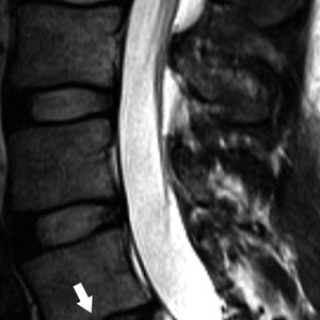

Artrose er sykdom i et synovialt ledd. Det synoviale leddet er et organ bestående av leddbrusk, subkondralt bein og en leddkapsel, som på innsiden er kledd med synovialmembran og på utsiden er forsterket av ligamenter. Sykdommer som primært rammer én av komponentene i et ledd, vil etter hvert medføre sekundære forandringer i de øvrige (fig 1), og det utvikles en leddsvikt som gir pasienten smerter og nedsatt funksjon. Alle ledd kan rammes, men artrose er vanligst i hånd, hofte og kne. Det følgende er en oversikt over epidemiologiske og patologiske forhold, årsaksmekanismer, utredning og...